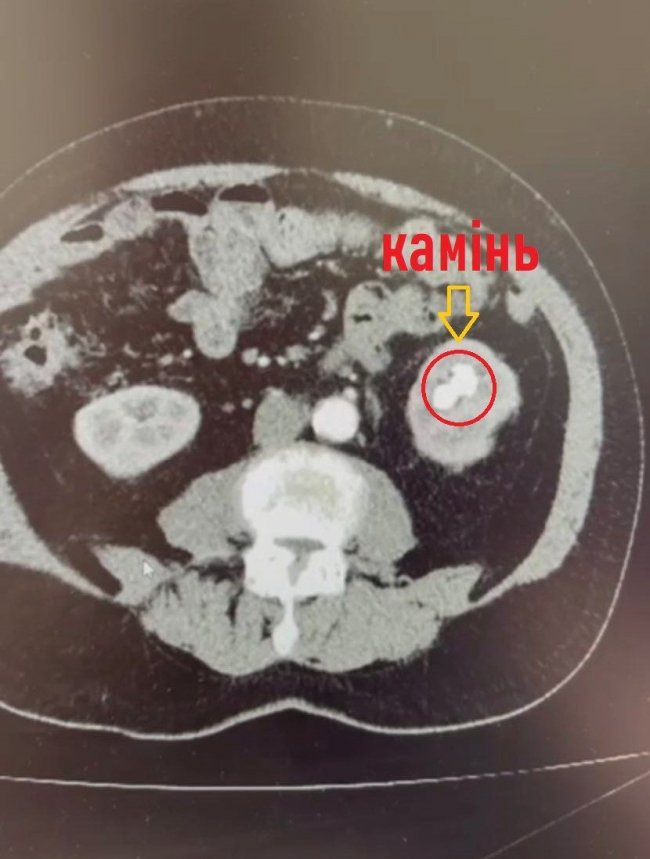

Обстеження на комп’ютерному томографі показали наявність в нирці коралоподібного каменя розміром 38х28 мм та доброякісного пухлинного утвору до 3 см в діаметрі з неоднорідним кровотоком у центрі, який знаходився на судинній ніжці лівої нирки.